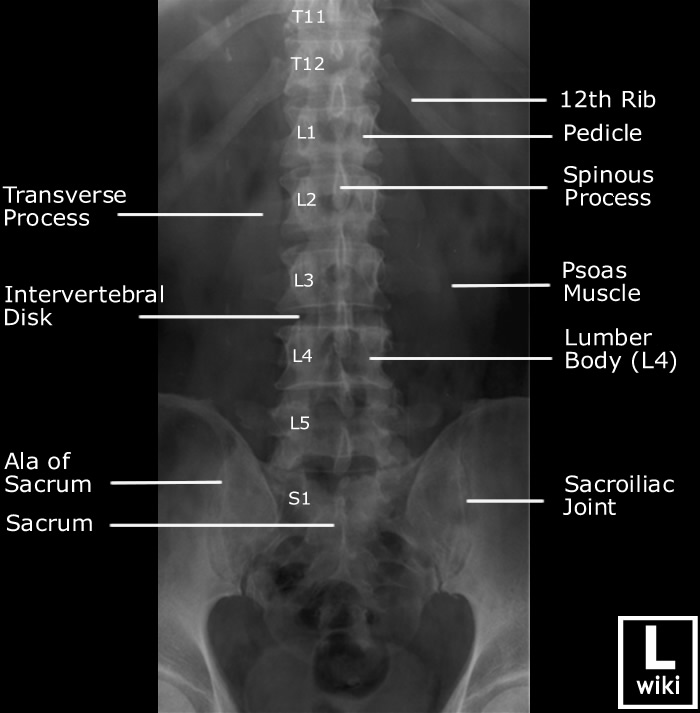

Spine Radiographic Anatomy

| AP view (Lumbar) | AP view (Sacrum) |